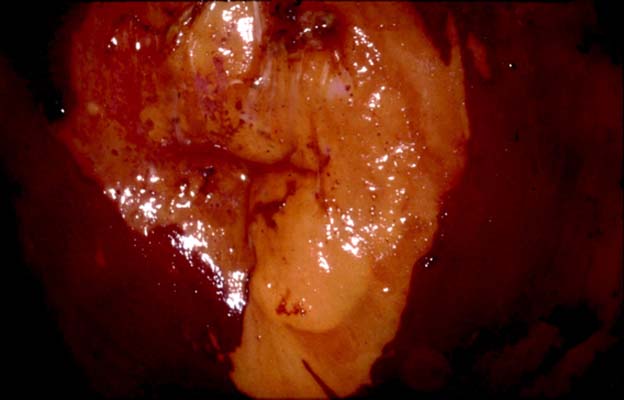

TAGII et TAGI : différence au lugol